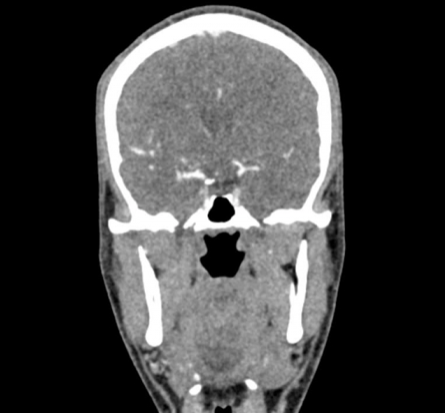

El maniquí de cabeza proporciona una simulación extremadamente realista de una angiografía por TC de cabeza y cuello (con contraste arterial) de un paciente con una malformación arteriovenosa en el lado derecho. El maniquí se entrega fiel a la escala original e incluye la columna cervical hasta la placa base de la quinta vértebra cervical.

Este fantasma se crea a partir de datos de pacientes reales y se fabrica con la última tecnología. Los huesos, vasos y tejidos blandos se muestran auténticamente con valores de TC realistas para todos los tejidos a un voltaje de tubo de 120 kVp en el TC. Si el maniquí se va a utilizar principalmente con otros voltajes de tubo (por ejemplo, 100 kVp), la calibración de los valores de CT se puede ajustar en consecuencia si es necesario. El fantasma proporciona contrastes de tejido realistas en las imágenes de rayos X. Los espacios aéreos se llenan con un material con aproximadamente -80 unidades Hounsfield.